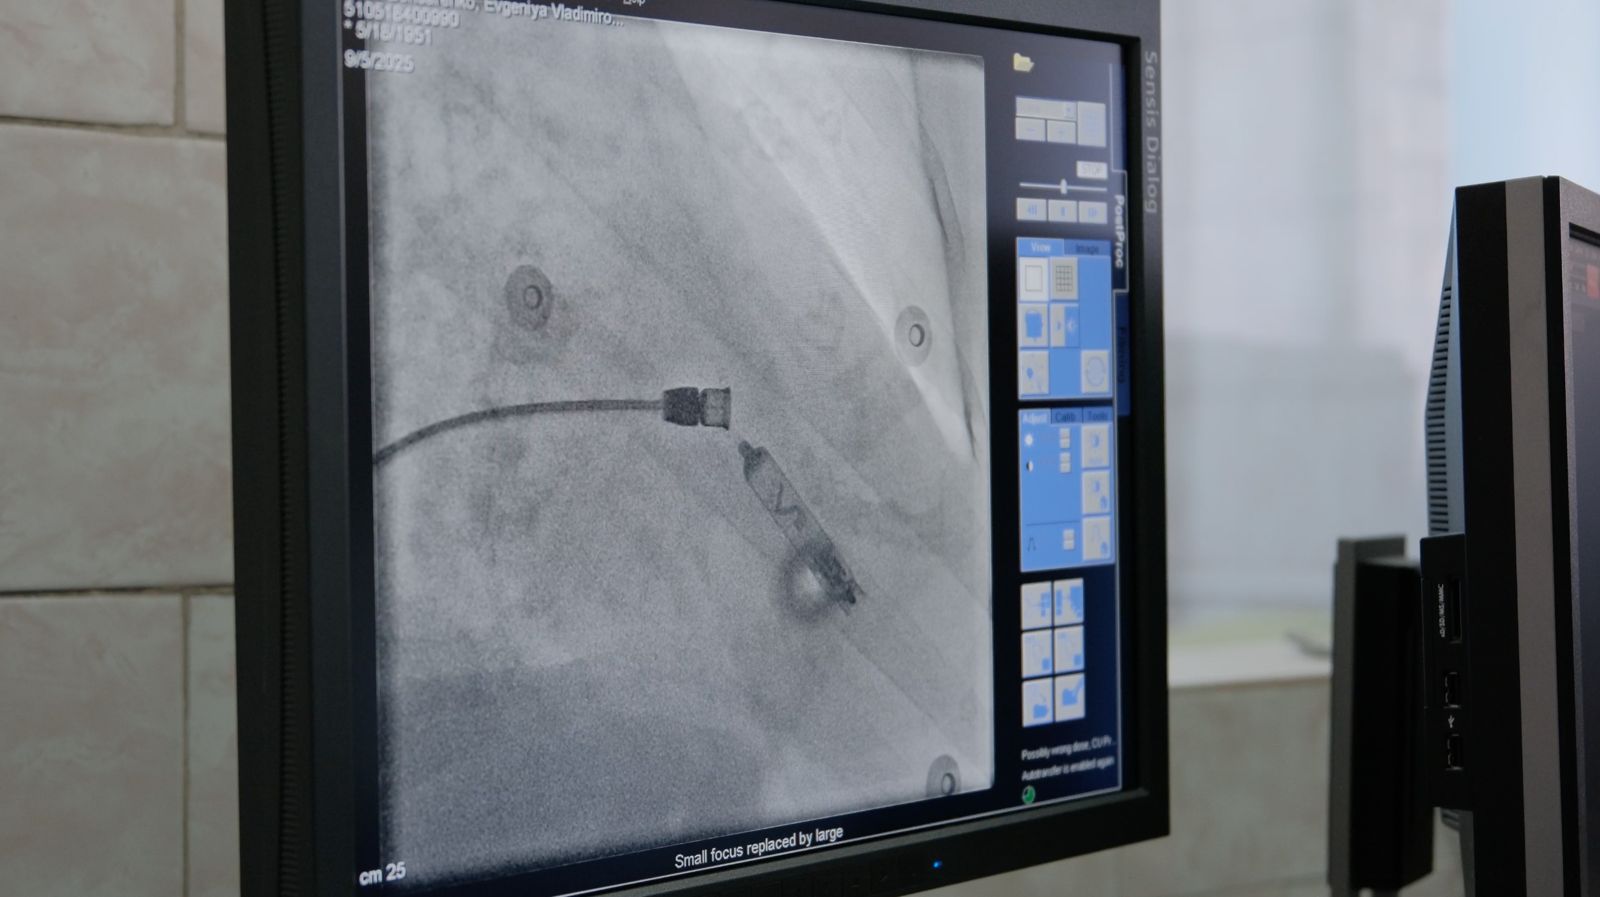

Кардиостимуляторларды орнату бойынша бірегей операция Қарағандыда жүргізілді

Фото Қарағанды облысы Денсаулық сақтау басқармасының баспасөз қызметінен алынды Бүгін, 5 қыркүйекте № 2 Қарағанды көпсалалы ауруханасында электродсыз электрокардиостимуляторларды (ЭКС) имплантациялау операциясы өтті. Бұл ауыр өткізгіштік бұзылыстары бар науқастарда қалыпты жүрекмағын тиімді қалпына келтіруге көмектесетін аритмологияның заманауи бағыты. Жаңа технологияны орнату бойынша Операция Қарағанды облысында бірінші болды, деп хабарлайды корреспондент ekaraganda.kz.

Электродсыз ЭКС, № 2 көпсалалы ауруханада түсіндірілгендей, инновациялық шешім болып табылады: құрылғы тамырлар арқылы электродтарды өткізбестен және тері астындағы қалтаны қалыптастырмай, тікелей жүрек қуысына имплантацияланады. Бұл тәсіл асқыну қаупін едәуір төмендетеді, оңалту уақытын қысқартады және операцияның өзі науқас үшін аз жарақат алады.

Жобаның мақсаты туралы айта келе, № 2 көпсалалы аурухананың хирург-аритмологы Нұрлан Елемесов: ең алдымен, бұл Қарағанды облысында жүрек-қан тамырлары ауруларын емдеудің озық технологияларын енгізуге және жоғары технологиялық медициналық көмектің қолжетімділігін арттыруға қатысты.

Операцияны Қазақстанның жетекші аритмологтарының командасы Abbott компаниясының серіктестерімен, сондай-ақ БАӘ мен АҚШ-тан шақырылған мамандармен бірге жүргізді. Интернационалдық дәрігерлер тобының пациенті Қарағанды тұрғыны Евгения Бондаренко болды. Әйел операцияға риза және дәрігерлерге өте риза – қорқыныш, дейді Ол, бірақ бәрі жақсы өтті. Қарағандылық өзін жақсы сезінеді.

"Құрылғының өзі жүрек ритағының күрделі бұзылулары бар науқастарға органның өткізгіштігін қалпына келтіруге және науқастың өмір сүру сапасын жақсартуға мүмкіндік береді. Құрылғы кішкентай, өлшемі екі сантиметр, ол жүректің оң жақ қарыншасына имплантацияланады. Операцияның өзі жарақатсыз, оңалтуды тездетеді: екінші күні Адам асқынусыз еркін қозғала алады", - деді Нұрлан Елемесов.

Сондай-ақ, дәрігер Қарағанды облысында кардиостимуляторларға мұқтаж пациенттер аз емес екенін айтты. Жылына екі жүзден астам құрылғы имплантацияланады, бірақ бүгін алғаш рет электродсыз электрокардиостимуляторларды имплантациялау операциясы болды.

Денсаулық сақтау министрлігінің Астанадан келген бас штаттан тыс аритмологы және қазақ аритмологтар қоғамының президенті Аян Әбдірахманов ЭКС технологиясы мүлдем жаңа, бірақ ол Қазақстанға келіп жатыр, ал операциялар оны бірнеше өңірлердегі – Астана, Алматы, Ақтау, Семей және Шымкенттегі пациенттерге жасады.

"Мұндай технология стимуляторлардың алдыңғы буындарымен салыстырғанда жақсы. Бұл төсекке және электродтарға байланысты асқынуларды азайтады. Бұл кішкентай құрылғы жүрекке феморальды қол жетімділік арқылы имплантацияланады. Ол төсек іріңдеуі, электродтардың сынуы және т.б. сияқты асқынуларды болдырмайды. Біз бұл технологияны одан әрі енгізуді жалғастырамыз", — деді Аян Әбдірахманов.

Электродсыз электрокардиостимуляторларды имплантациялау операциясы жарты сағатқа созылды және сәтті өтті-асқынулар болған жоқ, деп бөлісті БАӘ-дегі Abbott компаниясының клиникалық маманы Хадер Абу Халаф.

"Мұндай құрылғыны пациентке 20-25 жылға орнатуға болады – бірақ, әрине, оның қызмет ету мерзімі, оның ішінде иесінің өзіне және оған қаншалықты ұқыпты қарайтынына байланысты. Бірақ, әрине, қажет болса, мұндай стимуляторды жаңасына ауыстыруға болады", - деп бөлісті Хадер Әбу Халаф.